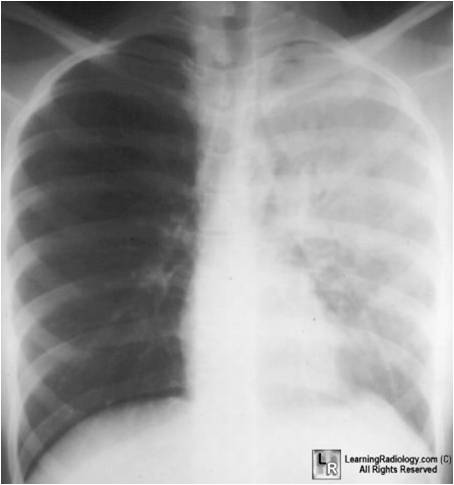

weekly clinical round for undergraduate from 8 to 11 AM during which interpretation of CHEST X rays was done for all cases of cardiothoracic surgery, gived by 2 staf member for 3 months